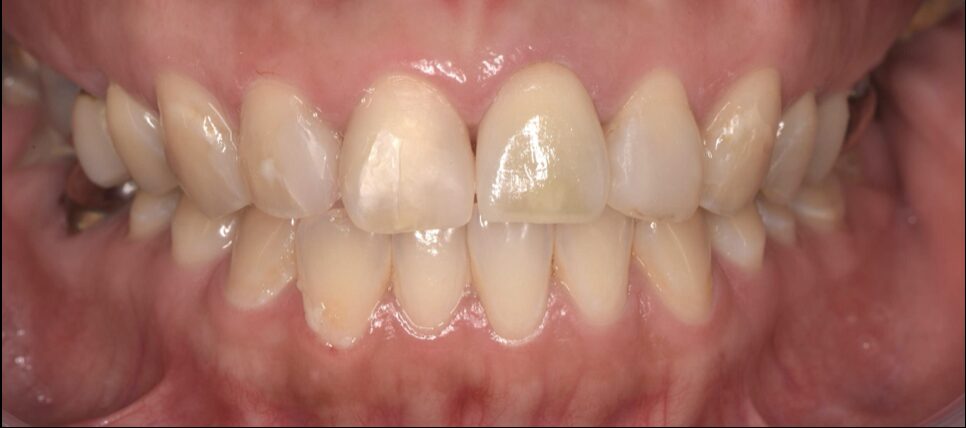

Before

初診時